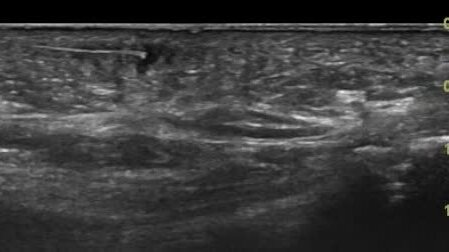

Инородное тело (заноза, игла кактуса) в мягких тканях стопы

Ультразвуковые находки от врача УЗД Зорина Я.П.